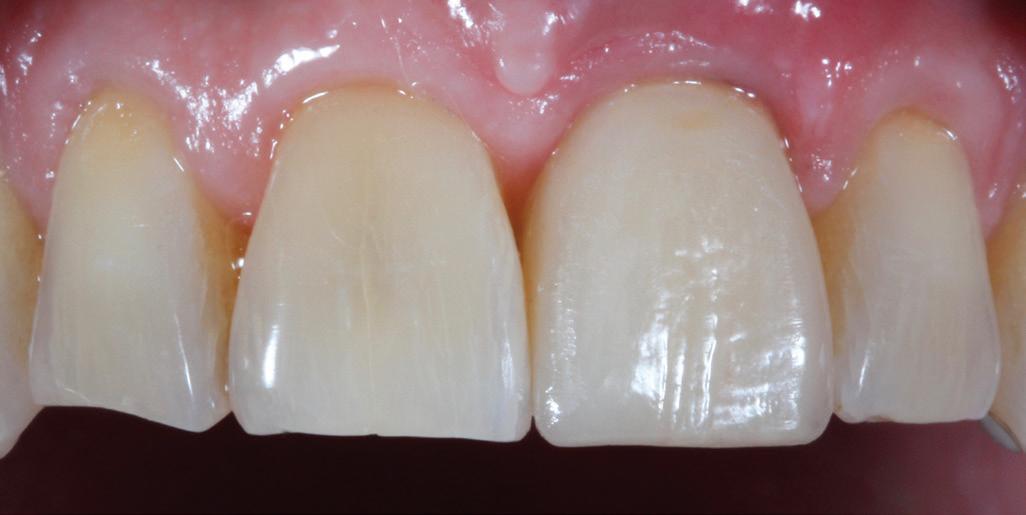

SITE AUGMENTATION Reconstituirea țesutului moale periimplantar și papilar în zona estetică

RECONSTITUIREA țesuturilor moi periimplantare. Scopul acestui raport de caz este de a demonstra procedurile chirurgicale utilizate pentru corectarea unui defect al țesuturilor moi periimplantare folosind țesutul moale interdentar în combinație cu tuberozitatea ca locație donatoare de țesut conjunctiv, utilizând o abordare prin tunelizare într-o zonă estetică.